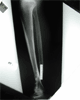

Follow

Up

Good bony union with preservation of ankle joint alignment